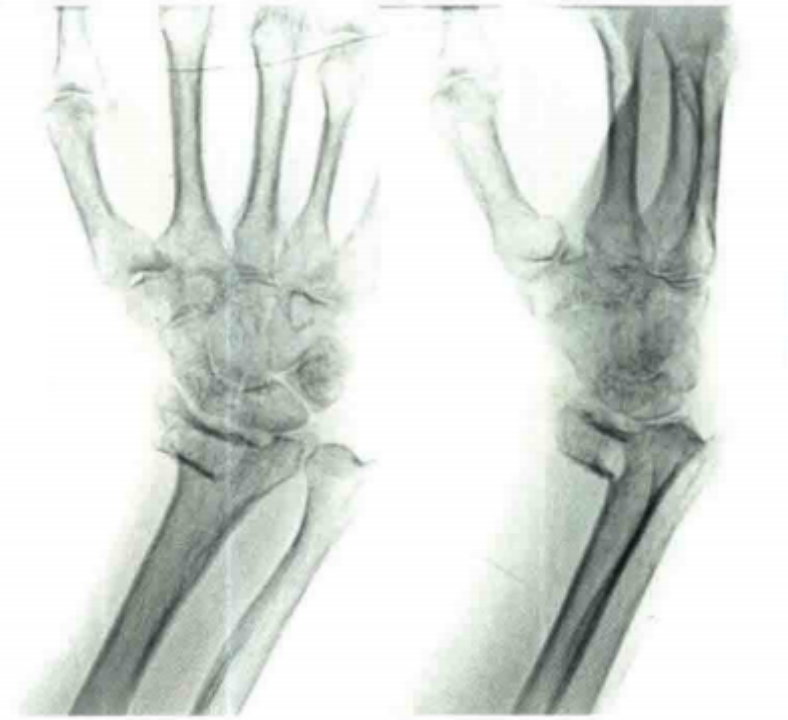

桡骨远端骨折

桡骨远端以骨松质为主,明显受骨质疏松症的影响。发病年龄自 45 岁开始,50~65 岁发病率剧增,65 岁以后降低,女性多于男性

此种骨折,闭经影响较增龄影响更明显。直接暴力和间接暴力均可造成桡骨远端骨折,但多为间接暴力所致。

医疗康复包括什么骨质疏松性骨折:诊断、治疗和康复一文整理!_https://www.jmylbn.com_新闻资讯_第24张

骨折后出现腕关节上方明显肿胀、疼痛,桡骨远端压痛明显,有纵向叩击痛,腕关节活动功能部分或完全丧失,手指作握拳动作时疼痛加重,有移位的骨折常有典型的畸形。

1、保守治疗

治疗方法一般采用手法复位,可用夹板或石膏固定或外固定器固定。

手法复位技巧:

通常采取闭合手法复位。首先背伸腕关节,向远端牵引,随后用拇指挤压远端骨折块的背侧,持续加压及牵引下慢慢伸直腕关节。